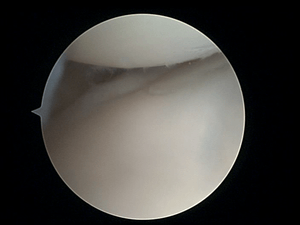

Arthroscopy (also called arthroscopic surgery) is a minimally invasive surgical procedure on a joint in which an examination and sometimes treatment of damage is performed using an arthroscope, an endoscope that is inserted into the joint through a small incision. Arthroscopic procedures can be performed to evaluate or treat many orthopaedic conditions including torn cartilage (known by health professionals as "meniscus"), torn surface (articular) cartilage, ACL reconstruction, and trimming damaged cartilage.

The surgical instruments are smaller than traditional instruments. Surgeons view the joint area on a video monitor, and can diagnose and repair torn joint tissue, such as ligaments and menisci or cartilage.

During an average knee arthroscopy, a small fiberoptic camera (the arthroscope) is inserted into the joint through a small incision, about 4 mm (1/8 inch) long. A special fluid is used to visualize the joint parts. More incisions might be performed in order to check other parts of the knee. Then other miniature instruments are used and the surgery is performed.[1]